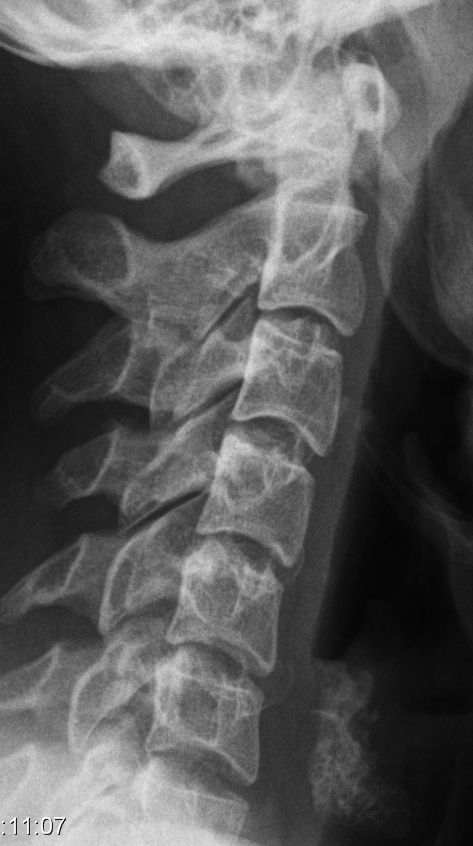

25-jährige Frau mit HWS-Distorsion. Steilstellung der HWS.

Schleudertrauma HWS-D, Halswirbelsäulendistorsion. Häufig durch PKW-Heckaufprall QTF-Score (Quebec Task Force): Schweregrad